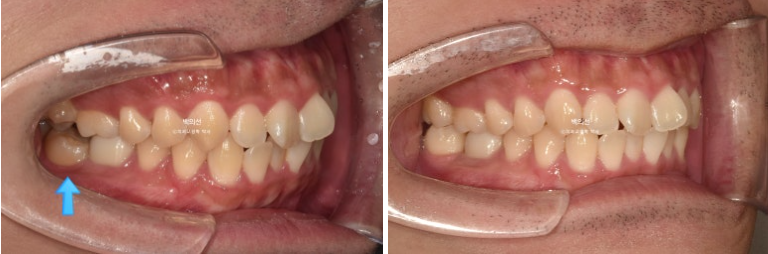

치료시작 6개월차, 쓰러진 큰어금니가 서고 가위교합이 해소가 되었습니다.

24.01~24.07

좌 치료 전 / 우 치료 후

24.01~25.05